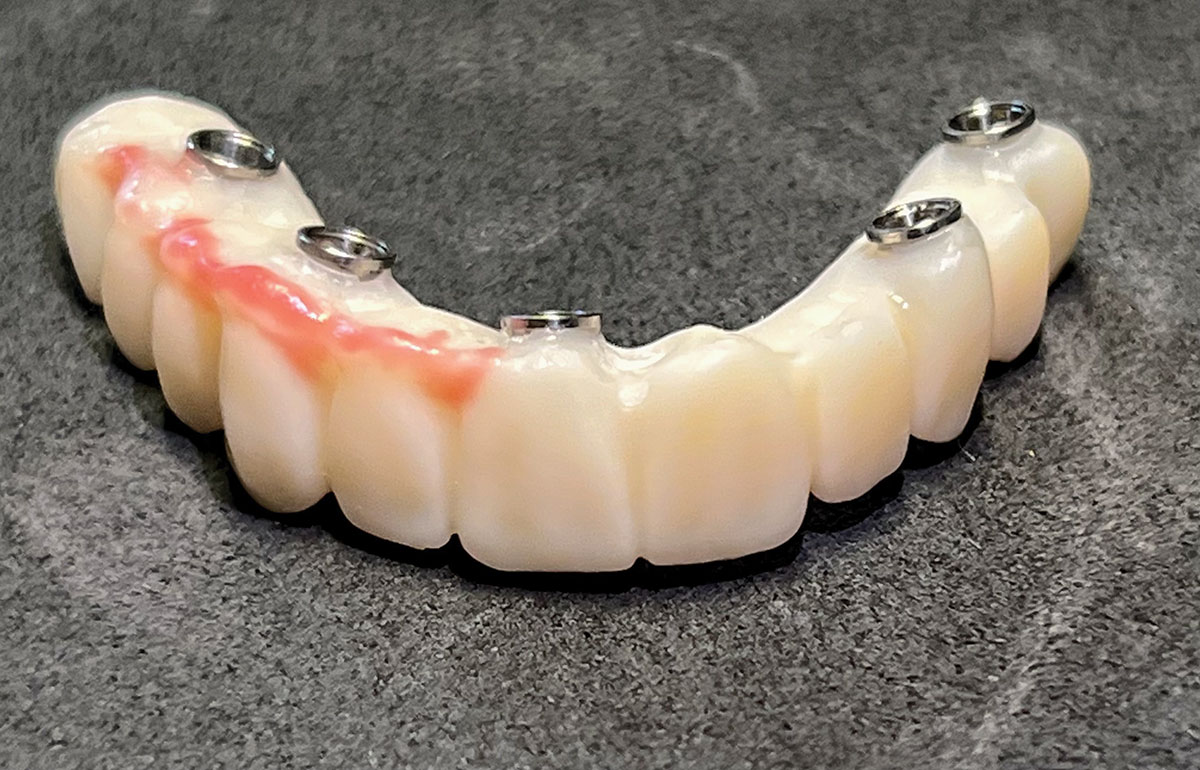

Fig 5. Maxillary provisional prosthesis printed and ti-bases inserted.

Figure 5

The implant company then returned an STL design file electronically via email. The office staff sent this file to the practice's 3D printer, and the appropriate color nanoceramic resin was used to print the prosthesis at 100 microns. Next, metal titanium (ti)-base cylinders, made specifically for the multi-unit abutments, were inserted into the prosthesis, which was then stained and glazed, and gingival color was applied to establish optimum esthetics (Figure 5).